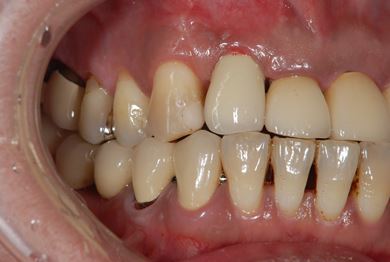

| 性別/年齢 | 女性 / 44歳 | ||||||||||||||||||||||||||||||||

| 主訴 | 上のさし歯がグラグラする。インプラントにした方が良いのか、相談したい。 | ||||||||||||||||||||||||||||||||

| 治療方針 | 抜歯と同時にインプラントを埋入し、治療期間を短縮する。 | ||||||||||||||||||||||||||||||||

| 治療内容 | インプラント2本(抜歯即日スピードインプラント)、メタルボンドセラミック2本 | ||||||||||||||||||||||||||||||||